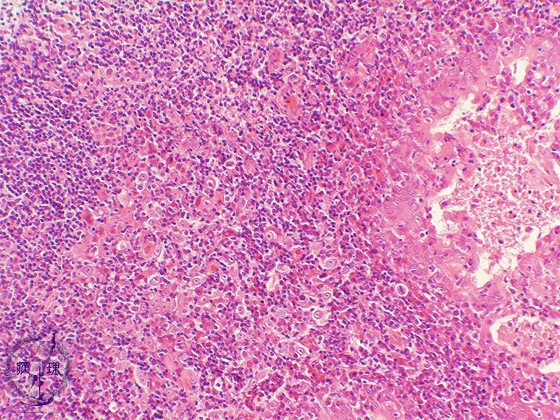

Microscopic view (intermediate power view): The most common subtype of nasopharyngeal carcinoma, undifferentiated carcinoma, is also known as elymphoepitheliomaf since there are abundant lymphocytes surrounding the carcinoma cells.